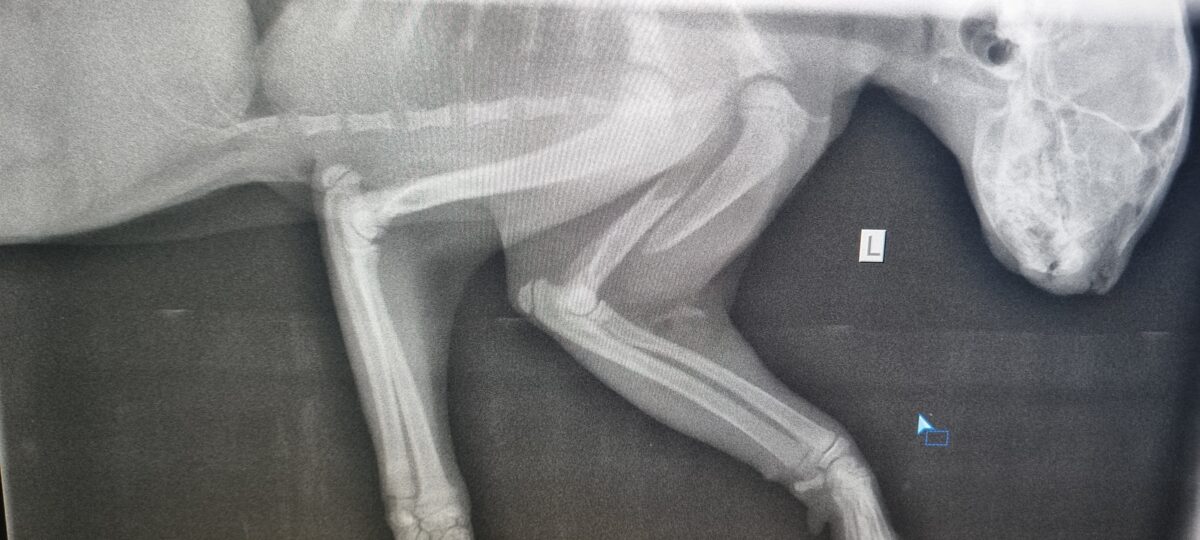

Veicam rentgenattēlu uzņemšanu Jūsu mīlulim

Vai vari atrast lūzumu kaulā?